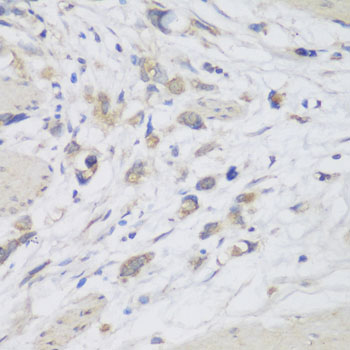

IHC (Immunohiostchemistry)

(Immunohistochemistry of paraffin-embedded human lung cancer using CEMIP antibody (AAA280732) at dilution of 1:150 (40x lens).)